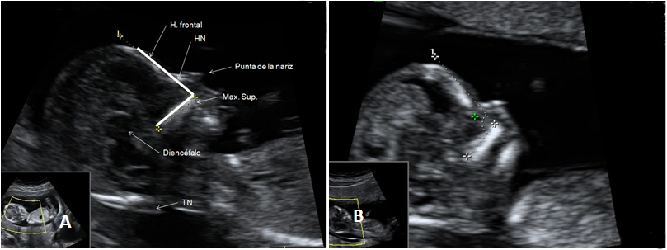

La insuficiencia tricúspide del feto se diagnostica con ecografía Doppler en la semana 12 de gestación. Es un marcador ecográfico de anomalías cromosómicas. Estudia el flujo de sangre que pasa a través de la válvula que une la aurícula derecha con el ventrículo derecho. Cuando da unos valores alterados se recomiendan otras pruebas más invasivas para verificar que el bebé no sufre síndrome de Down.

Insuficiencia tricúspide

Doppler pulsado en la válvula tricúspide. Registro normal (imagen A) y registro con insuficiencia (imagen B con flechas).